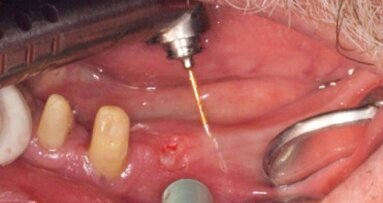

Irygacja

Po oczyszczeniu i uformowaniu wszystkie kanały przepłukano ostatecznie przy użyciu igieł niklowo-tytanowych w rozmiarze 30 G (Stropko NiTi Flexi-Tip, SybronEndo), które wprowadzano na głębokość o 1-2 mm mniejszą od długości roboczej. Kanał płukano 2 ml odpowiedniego roztworu: 17% EDTA (Roth International), 2,5% NaOCl, MTAD (BioPure MTAD, DENTSPLY Tulsa) lub 2,0% chlorheksydyną. Tę samą metodę stosowano dla wszystkich 20 zębów w każdej grupie, zmieniając tylko odpowiednio badany płyn. Po oczyszczeniu i preparacji osuszano kanały chłonnymi sączkami papierowymi (DENTSPLY Maillefer).